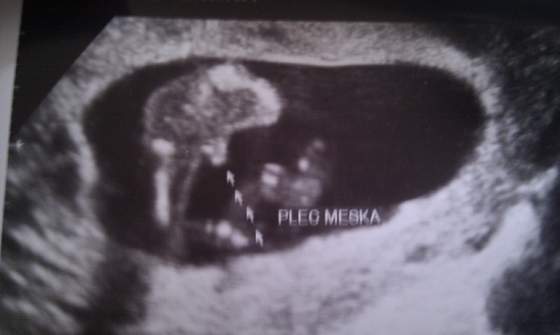

Wiec tak jak pisałam na ogólnym będziemy mieli chłopca

. Nasz synus całą wizytę kleczal na kolanach jakby pokutę odrabial

. Ogólnie wszystko w porządku. Idzie wszystko dokladnie tak jak wg terminu z OM. Maluch waży już 129 g i mierzy prawie 10 cm ( długość od czubkaglowy do pupy-bez nóżek). A oto fotki: